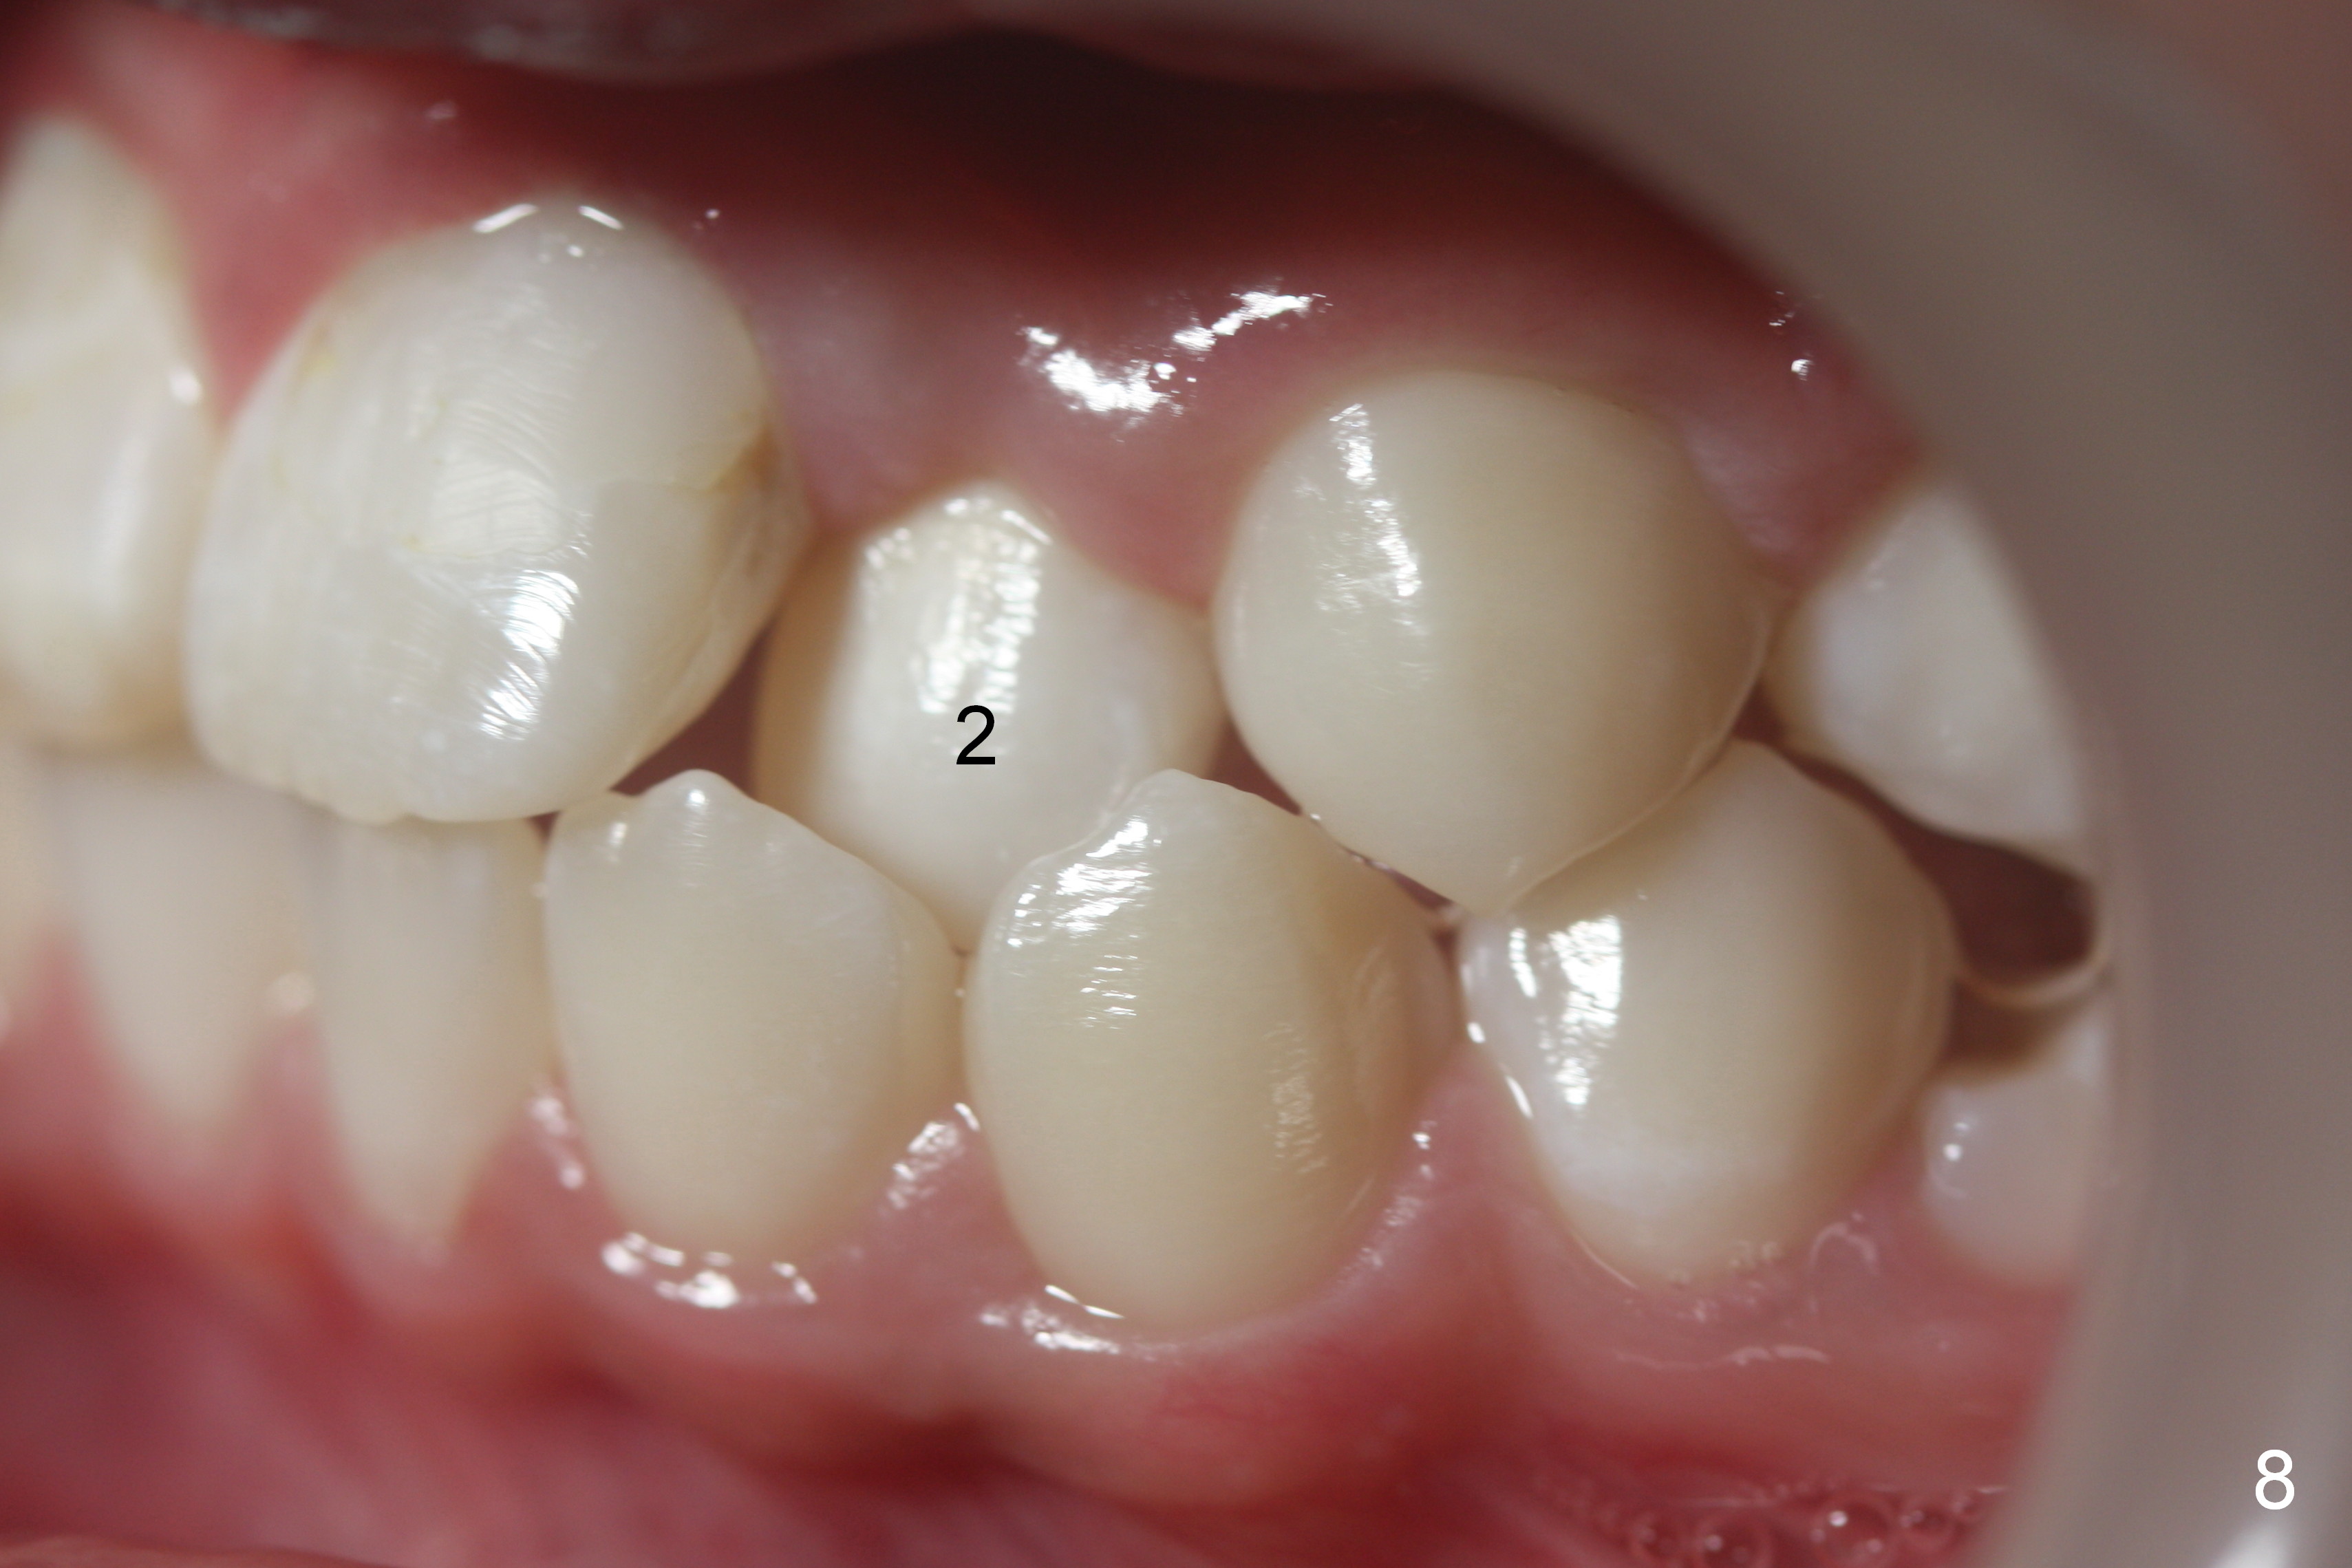

No brackets are placed at UR, UL, and LR 2 (blocked out, Fig.6,8) initially. Open coil spring is placed to gain the space with .018 stainless steel wires. When the space is almost achieved, sling shot is installed for labialization. When the space has been completely achieved and the lateral is almost in the normal position, place the bracket upside down.

Another 1 month, the right canines (Fig.14: 3, as compared to the left side (Fig.15)) occlude each other, while LR2 has full engagement into .016 niti wire (compare to Fig.12,13). Open coil springs are placed with upper .018' ss arch wire. It must be easier to gain space for UR 2 (Fig.16) than UL2 (Fig.17), because of the presence of space on the right side (4 in Fig.16). There appears no space between UL 4 and 6.

Three visits after open coil spring and 1 visit after sling shot, U2 cross bite is corrected (Fig.18,19). Due to UR2 rotation (Fig.19), bracket cannot be placed (Fig.20, 16 niti). Power chain x 3 is placed between UR2 and 3 to gain space for bracketing, which turns out not working. UL2 bracket is placed upside down for torque.